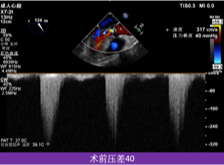

植入后超声评估:

超声评估血流动力学改善明显